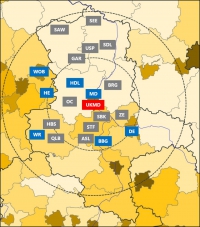

Die Stroke Unit des Universitätsklinikums Magdeburg behandelt im Jahr etwa 1000 Patienten und Patientinnen mit einem Schlaganfall und ist damit die größte derartige Einheit im Norden Sachsen-Anhalts mit regionalen und überregionalen Partnerschaften über Landesgrenzen hinaus (Abbildung 1). Wir bieten rund um die Uhr State-of-the-Art-Therapien mit Fokus auf endovaskulären Rekanalisationsverfahren von Verschlüssen großer Hirngefäße zusammen mit dem Team der Neuroradiologie. Durch Teilnahmen an nationalen und internationalen Studien erfolgt eine stetige Weiterentwicklung von Therapien, um die Akutbehandlung und Sekundärprävention von Schlaganfällen zu optimieren.